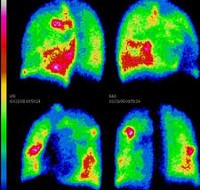

Сцинтиграфия легких проводится для определения регионарной вентиляции и легочного капиллярного кровотока. Процедура назначается после рентгенографии грудной клетки. Исследование показано при подозрении на легочную эмболию, ателектаз, пневмосклероз, пневмонию, новообразования, обструктивные процессы и другие патологические состояния.